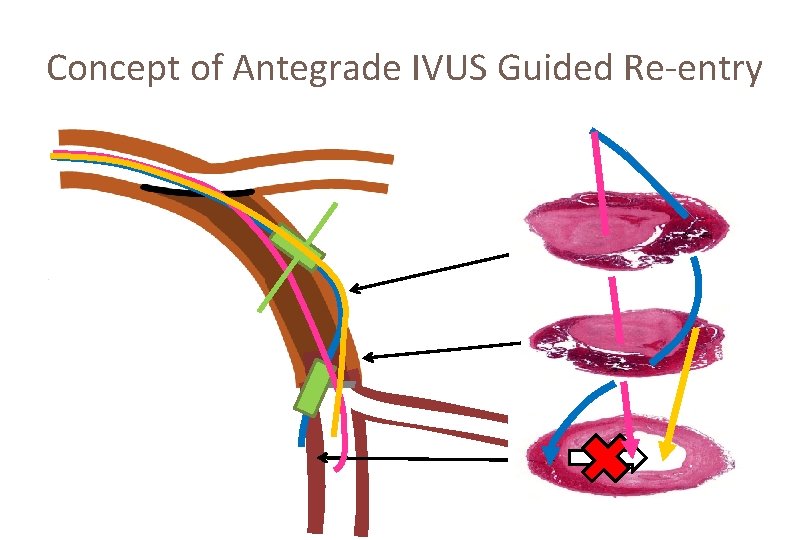

Concept of Antegrade IVUS Guided Re-entry